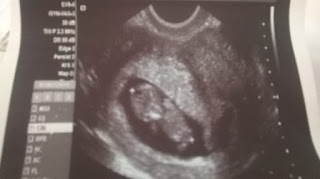

![]() |

| Első kép Zsófiról |